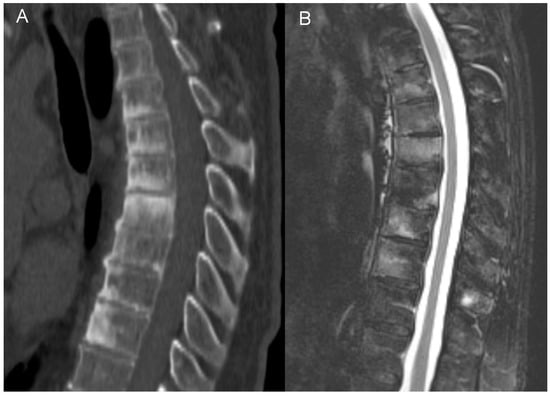

Interestingly, in three patients we have observed the features of pseudoarthrosis in an ankylosed spine (unstable Anderson lesion), a finding that to the best of our knowledge has not yet been reported in patients with CNO/SAPHO syndrome. All pseudoarthroses occurred in the thoracic region and, in one patient, pseudoarthrosis was associated with an aggravation of pain (Figure 6). This observation suggests that in patients with a longstanding CNO and the worsening of symptoms the radiologist should look for a developing pseudoarthrosis, just like in patients with a longstanding AS or with DISH [66].

Figure 6.

Unstable Anderson lesion in a 65-year-old patient with SAPHO syndrome. Sagittal CT reformat (A) and MRI (B) shows interruption of syndesmophytes and disc space widening (arrows).